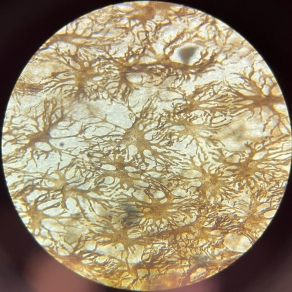

Reticular Connective Tissue (Lymph Node)